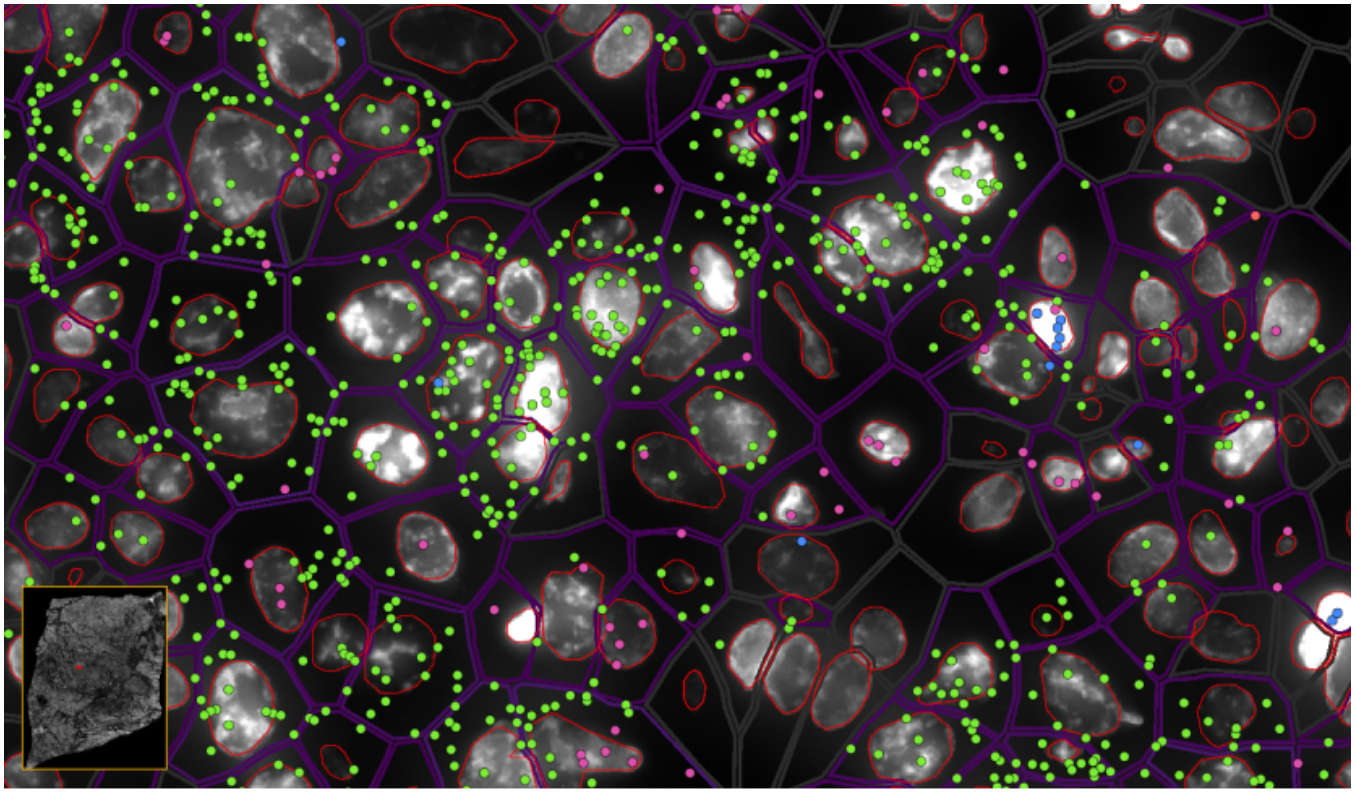

ͼ6-1£ºÊµÏÖµ¥Ï¸°û/ÑÇϸ°ûÇø·ÖÂʵĿռäת¼×éÆÊÎö£¬£¬£¬£¬£¬Â̵ã-EPCAM , À¶µã-KLRD1 £¬£¬£¬£¬£¬·Ûºìµã-LILRB2

ͼ6-2£ºÊµÏÖµ¥Ï¸°û/ÑÇϸ°ûÇø·ÖÂʵĿռäת¼×éÆÊÎö£¬£¬£¬£¬£¬Â̵ã-EPCAMת¼±¾